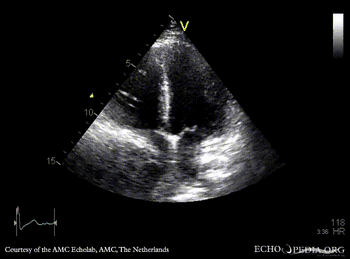

Compression of right atrium

A4CH: Compression of right atrium by aneurysm of ascending aorta PLAX: large aneurysm of ascending aorta, Bentall in situ